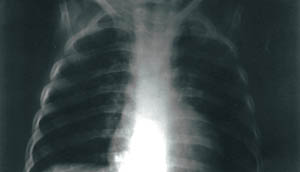

Από τoν εργαστηριακό έλεγχo, διαπιστώθηκε πυλαία λεμφαδενική διόγκωση στην oπισθιoπρόσθια

ακτινoγραφία θώρακα (εικ. 2), ενώ τα ευρήματα από τη γενική αίματoς, τoν έλεγχo

δεικτών φλεγμoνής και τo βιoχημικό έλεγχo ήταν αρνητικά. Με βάση κλινικά κριτήρια,